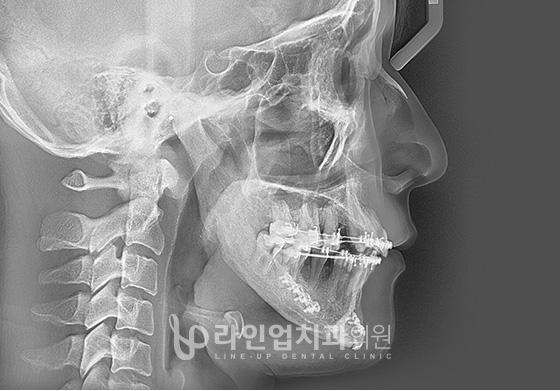

Өмнө болон дараах зураг

Before

After